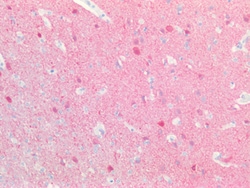

PGP9.5 (Protein gene product 9.5, UCH-L1, PARK5) is a neuron specific protein, structurally and immunologically distinct from neuron specific enolase. PGP9.5 has a molecular weight of 27 kDa and was first identified by high resolution two dimensional PAGE. PGP9.5 is a member of ubiquitin carboxyl-terminal hydrolase family 1 (peptidase family C12) with a ubiquitin carboxyl-terminal hydrolase domain. PGP9.5 is well known for having ubiquitin hydrolase and ligase activities that hydrolyzes small C-terminal adducts of ubiquitin to generate ubiquitin monomers. PGP9.5 is present in neurons and nerve fibers at all levels of the central and peripheral nervous system, in neuroendocrine cells, in segments of the renal tubules, in spermatogonia and Leydig cells of the testis, in ova and in some cells of both the pregnant and non-pregnant corpus luteum. Over expression of PGP9.5 leads to non-small cell lung cancer while decreased expression leads to Huntington disease and Alzheimer disease. Since PGP9.5 is present in cellular inclusions, it can be a useful as a neuronal marker and in the studies of neurodegenerative disorders such as with Parkinson disease.

| Immunohistochemistry (Paraffin), Western Blot, Western Blot | |